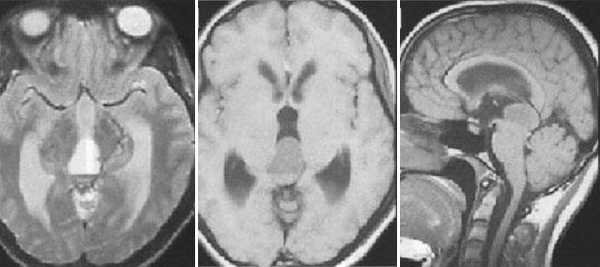

Герминома пинеальной области. На Т2 ВИ опухоль имеет слабо гиперинтенсивный сигнал по сравнению с тканью мозга, тогда как на Т1 опухоль практически изоинтенсивна с мозгом. Желудочковая система гидроцефально расширена. III желудочек деформирован. Четверохолмная пластинка оттеснена кзади.

Герминома пинеальной области. Опухоль имеет гетерогенное строение с множеством мелких и крупных кист. Вокруг опухоли определяется перифокальный отек.